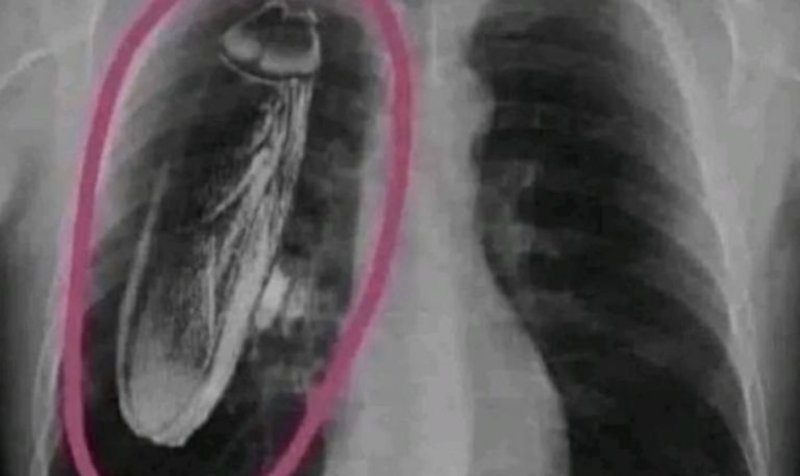

¿Una cucaracha en los pulmones? Radiografía de terror dejó a todos sin palabras…

Un hombre acudió a un hospital a realizarse una radiografía del tórax y el resultado alertó a los médicos, pues al colocar la placa en la luz de los rayos X, reveló que tenía nada más y nada menos que... ¡una cucaracha gigante en los pulmones! Hemos visto casos de tenedores o cuchillos o hasta objetos extraños que no sabemos cómo llegan a nuestro estómago o a otras partes del cuerpo, pero que una cucaracha del tamaño de un pulmón aparezca en una radiografía, es poco común.

Sin embargo, esto no era en realidad lo que parecía. Aunque el hombre fue enviado a un hospital en otro país para descubrir no sólo cómo había llegado esa cucaracha a su cuerpo, sino también porque no tenían la infraestructura para operarlo debido al extraño tamaño del animal, la realidad alertó a todos: en su cuerpo y tras la última radiografía, la cucaracha gigante había desaparecido.